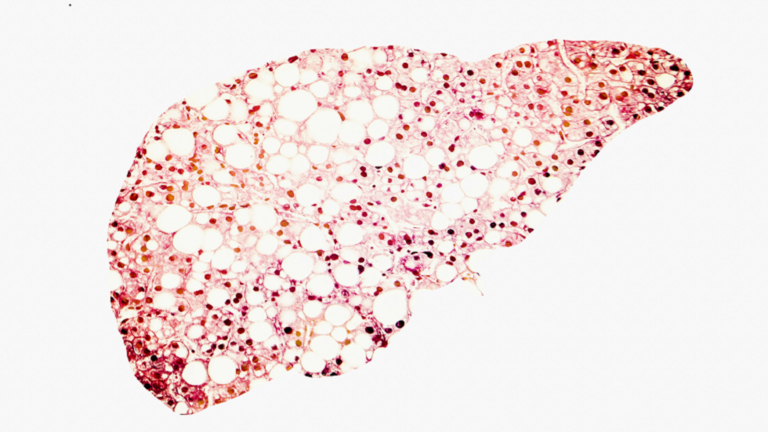

علامة تحذيرية خطيرة في بطنك قد تدل على اصابتك بـ الكبد الدهني!